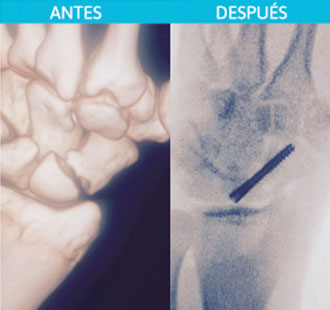

Fractura del hueso escafoides.

Después: Colocación mínimamente invasiva de tornillo para fijación de la fractura